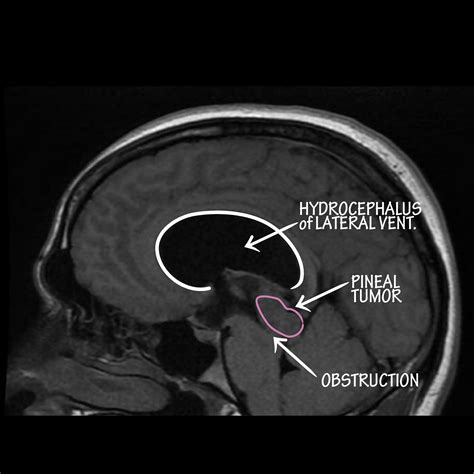

Hydrocephalus is a condition characterized by the accumulation of cerebrospinal fluid (CSF) in the brain, leading to increased intracranial pressure. Among the various types of hydrocephalus, Non Communicating Hydrocephalus is a significant subtype that requires careful understanding and management. This condition, often referred to as Non Communicating Hydrocephalus Amboss, involves an obstruction within the ventricular system of the brain, preventing the normal flow of CSF. This blog post delves into the intricacies of Non Communicating Hydrocephalus, its causes, symptoms, diagnosis, and treatment options.

Non Communicating Hydrocephalus, also known as obstructive hydrocephalus, occurs when there is a blockage in the pathways that allow CSF to flow within the brain. This blockage can be caused by various factors, including tumors, infections, congenital malformations, or head injuries. Unlike communicating hydrocephalus, where the obstruction is outside the ventricular system, non-communicating hydrocephalus specifically affects the ventricles themselves.

• Tumors: Brain tumors, especially those located in the posterior fossa or near the ventricles, can obstruct the flow of CSF.

• Imaging Studies: Imaging techniques such as computed tomography (CT) scans and magnetic resonance imaging (MRI) are crucial for visualizing the brain and identifying any obstructions or abnormalities in the ventricular system.